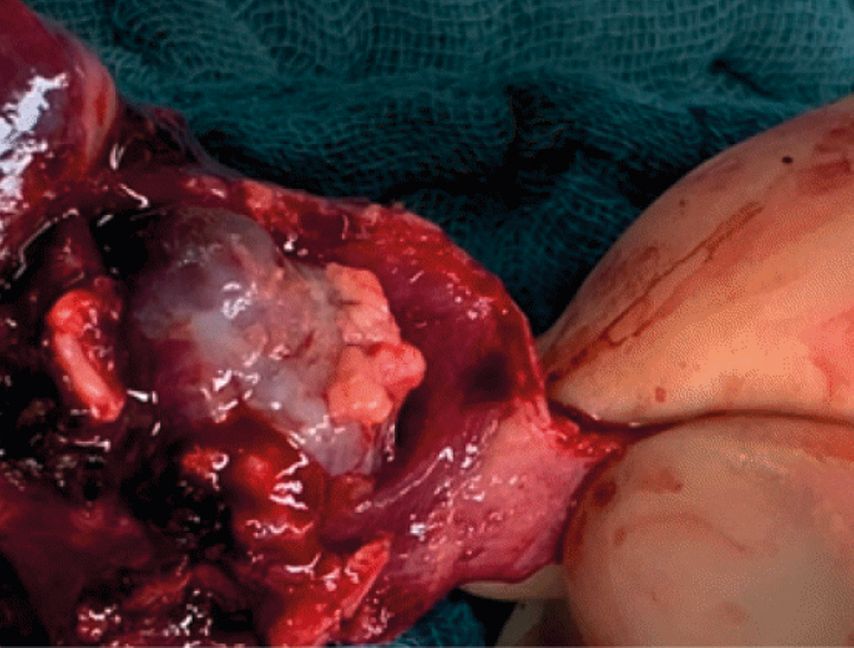

Aufgrund der Mitbeteiligung des rechten Mittellappenbronchus erfolgten in unserem Fall, bei suspekten Mediastinal-Lymphknoten, die komplikationslose Entfernung des rechten Mittel- und Unterlappens sowie eine mediastinale Lymphadenektomie (Abb. 5). Der postoperative Verlauf gestaltete sich komplikationslos. In den bisherigen Verlaufskontrollen zeigt sich kein Anhalt für ein Rezidiv (Abb. 6).

Besonderer Dank gilt Dr. med. Tatjana Manuylova und Dr. med. Justus Lieber, Universitätsklinik Tübingen, für die Bereitstellung der Abbildungen 4 und 5.